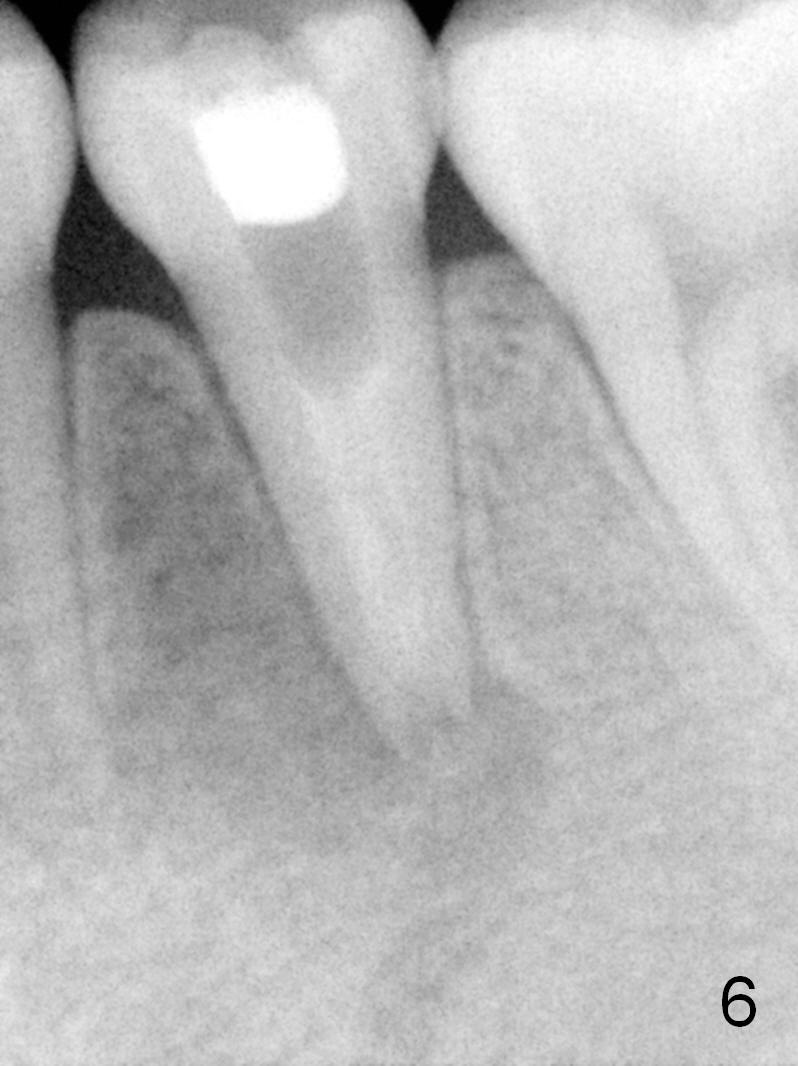

A 13-year-old girl has a buccal apical fistula at the tooth #20 with large periradicular radiolucency (Fig.1 *). After canal debridement, calcium hydroxide paste is placed in the canal (Fig.2 *). One month later, the fistula does not disappear with light percussion. New paste is placed (Fig.3). Two months later, the fistula disappears without percussion. The existing paste (Fig.4) is changed (Fig.5 (yellow: radiolucency; red: Inferior Alveolar Canal)). Another 2 months later, the fistula does not recur; as before, the paste density decreases, so does periradicular radiolucency (Fig.6). Root canal is packed (Fig.7). Six months postop, periradicular radiolucency continues to decrease, while the lamina dura at the apex is discontinuous (Fig.8 between arrowheads). Seven years postop, the lamina dura at the apex is seemingly intact (Fig.9). The patient remains asymptomatic at #20. In fact there is an acute infection at #29.